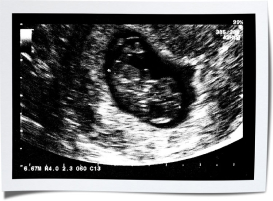

УЗИ на 7 неделе беременности

7 недель — это немного раньше стандартного срока для УЗИ. В большинстве клиник первое сканирование беременной женщины проводится между 8 и 14 неделями. За ним обычно следует новое сканирование на 18–21 неделе. Если же врачу нужны какие-либо дополнительные сведения, уточнение срока или подтверждение того, что вы носите двойню, он назначит УЗИ на 7 неделе беременности. Помимо того, что врач оценит развитие, измерит все размеры и уточнит срок беременности, он сделает вам на память фото плода. Его можно разместить в альбоме с фото и видео ваших изменений в период ожидания.